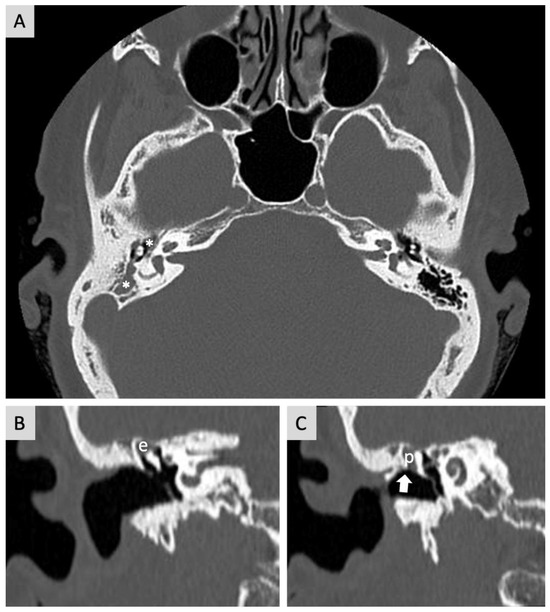

Axial (horizontal) CT of the right temporal bone showing cholesteatoma... Download Scientific Cholesteatoma And Tympanometry chronic otitis media (com) is a recurrent infection of the middle ear and/or mastoid air cells in the presence of a. other causes are increased stiffness of the eardrum (from scarring), tympanosclerosis (the formation of dense connective tissue around. cholesteatoma is clinically defined as an abnormal extension of skin into the middle ear and mastoid air cell. Cholesteatoma And Tympanometry.

Bilateral cholesteatoma Image Cholesteatoma And Tympanometry chronic otitis media (com) is a recurrent infection of the middle ear and/or mastoid air cells in the presence of a. cholesteatoma is clinically defined as an abnormal extension of skin into the middle ear and mastoid air cell spaces. cholesteatoma is an accumulation of squamous epithelium and keratin debris that usually involves the. patients with. Cholesteatoma And Tympanometry.